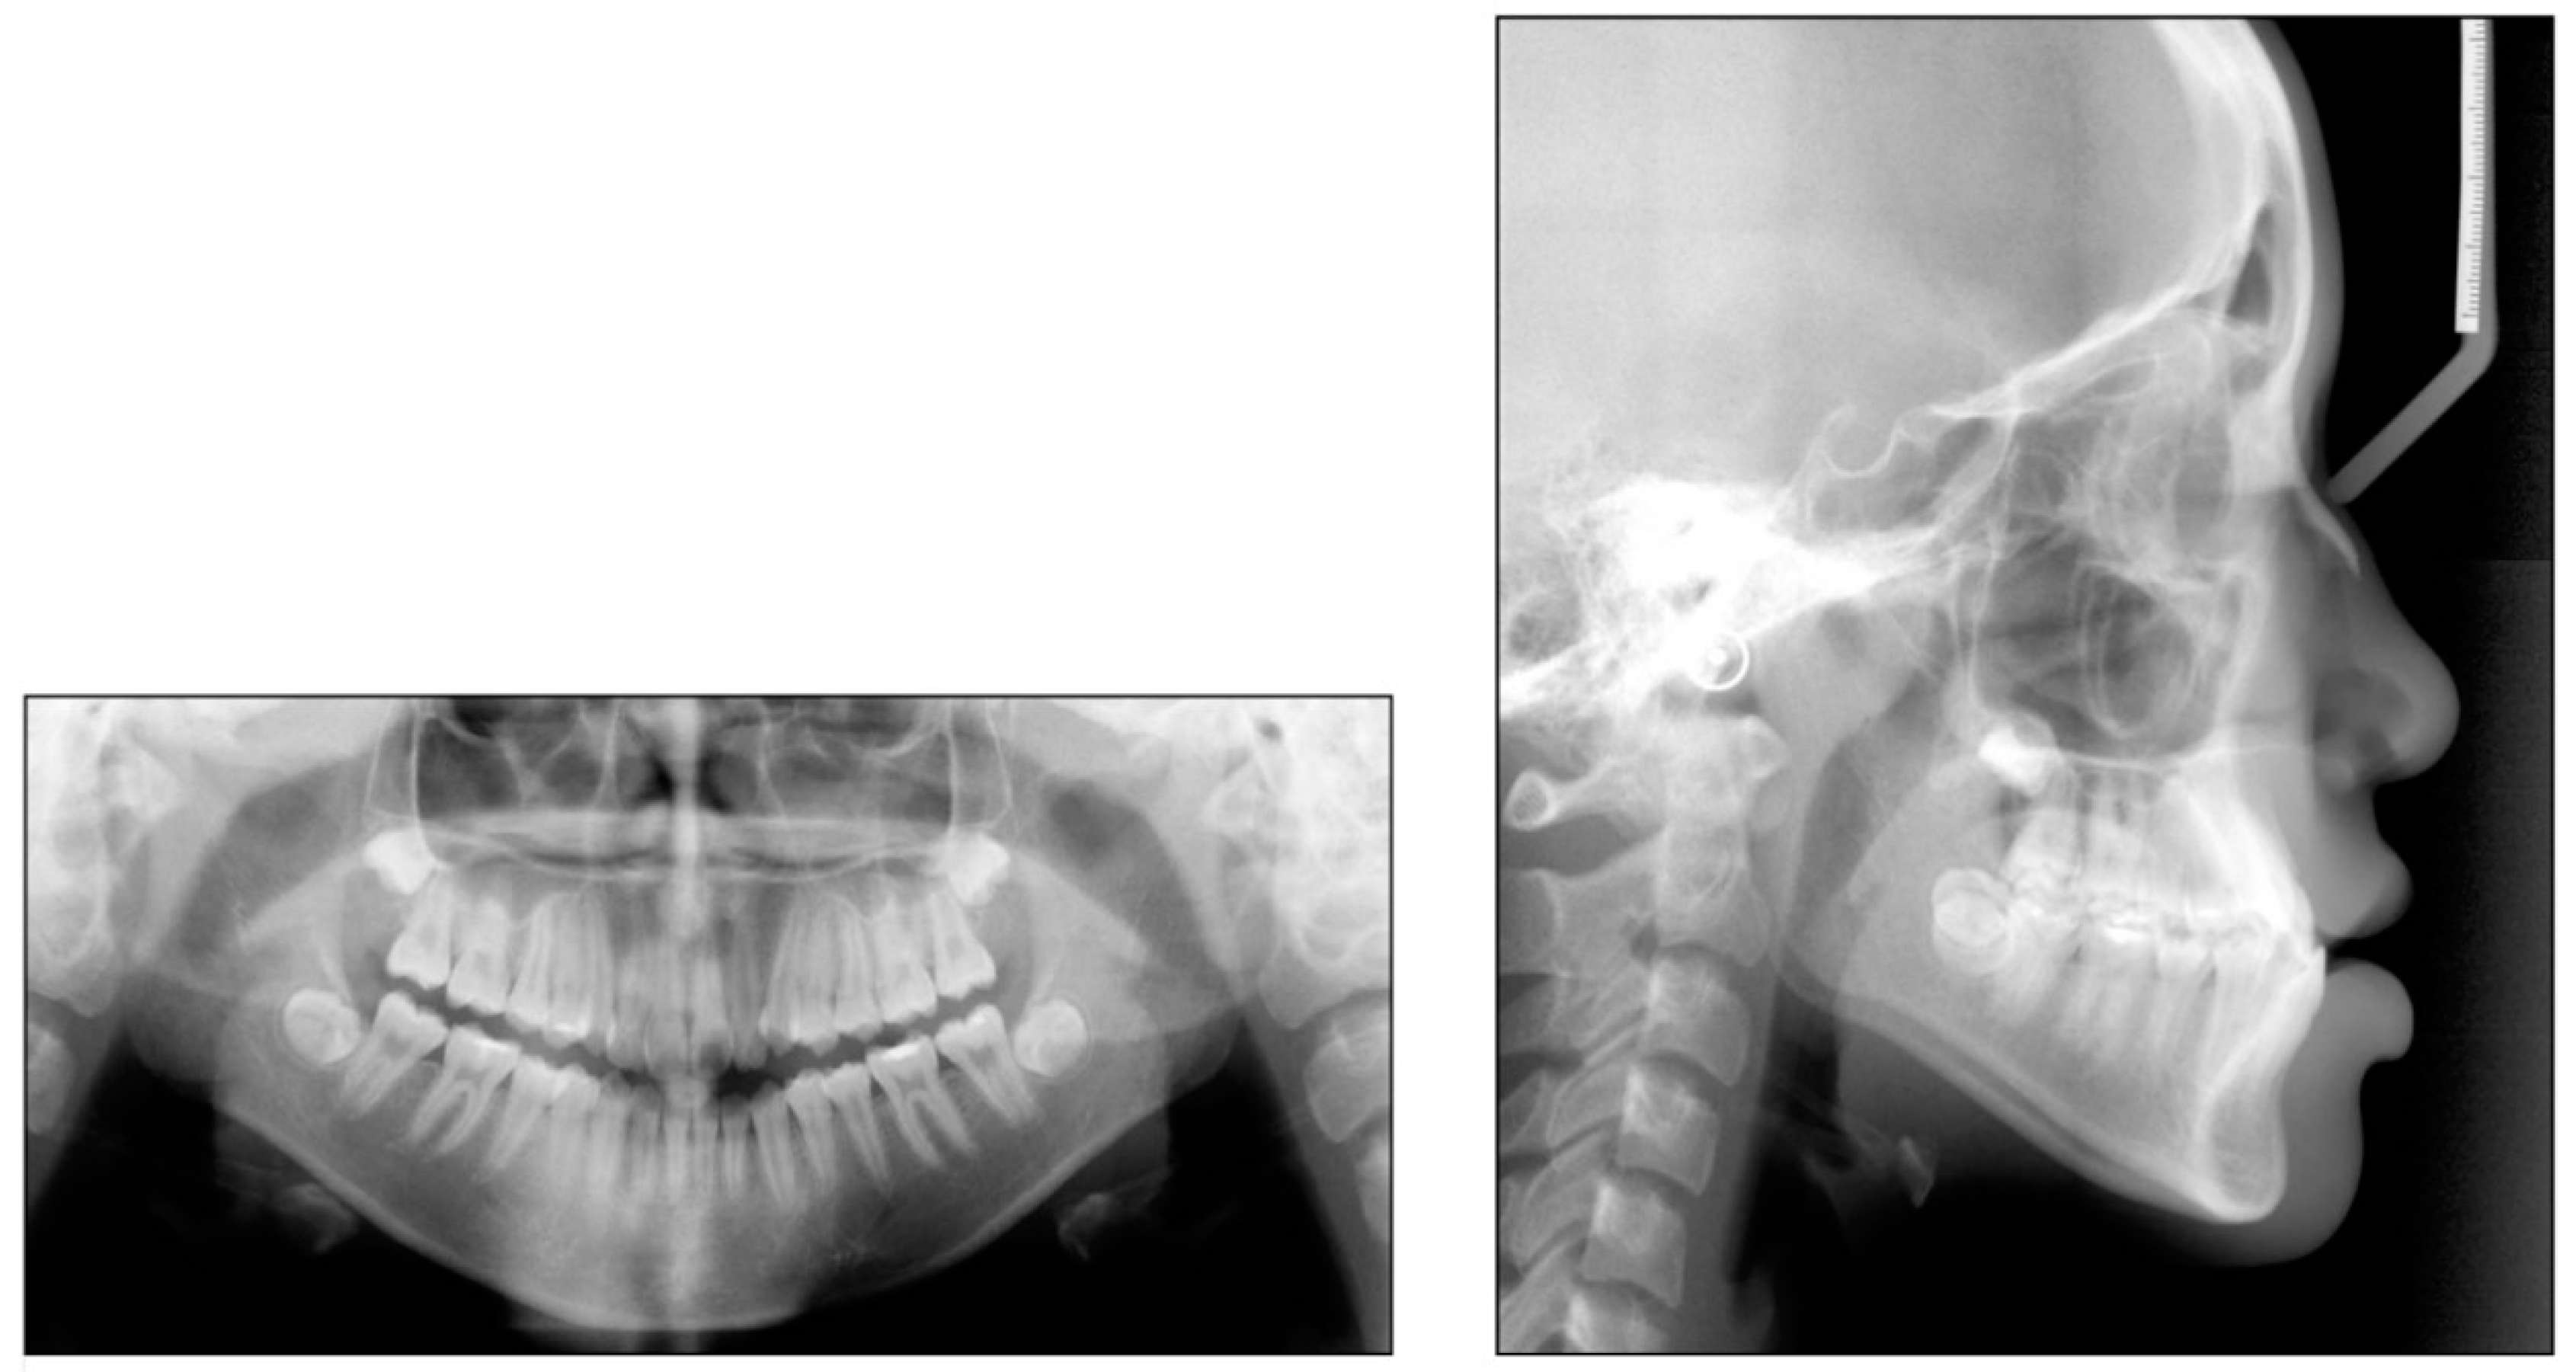

2. Case 1

2.1. Diagnosis and Etiology